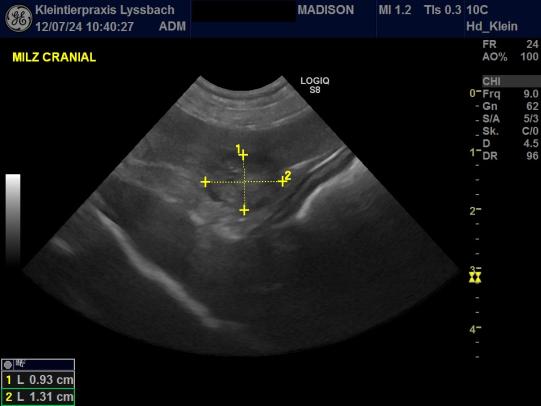

Obwohl zu erwarten ist, dass die Wurzel des abgebrochenen Schneidezahnes noch im Kiefer sitzt, ist die entsprechende Stelle im Maul optisch unauffällig am heilen, komplett schmerzfrei und scheint als Ursache für das Problem unwahrscheinlich. Nun wird eine zweite Etappe Diagnostik durchgeführt: Die angefertigten Bruströntgen des Hundes sind unauffällig; im Ultraschall der Bauchhöhle wird aber ersichtlich, dass die Milz einen Knoten von ca 10 x 13 Millimetern Durchmesser aufweist. Die Struktur des Knotens ist "löchrig" - ein Zeichen für bluthaltige kleine Kavernen, ein typisches Bild beim gefürchteten Hämangiosarkom. Dieser bösartige Tumor bildet sich aus Blutgefässen und ist insbesondere bei älteren grossrassigen Hunden in der Milz zu finden. Könnte dieser Knoten den reduzierten Appetit von Madison erklären? Leider ist es sehr schwierig und auch riskant, mittels Biopsierung herauszufinden, um was für Gewebe es sich beim Knoten handelt. Wir entschliessen uns, die Milz zu entfernen - eine relativ problemlose, kurze Operation; und ohne Milz kann der Hund gut leben. In derselben Narkose wird auch noch gleich der verbliebene Wurzelrest des Schneidezahnes entfernt.